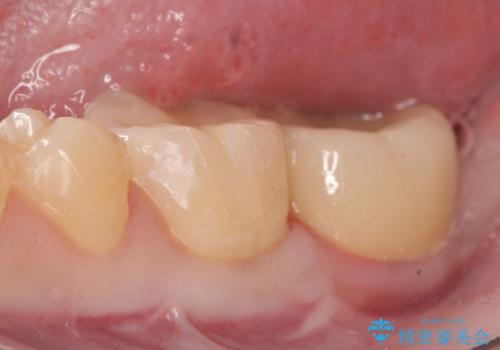

- 左下奥歯がしみるといらっしゃった方の症例です。

左下7の虫歯は深く、また歯冠高径も低かったため、歯冠長延長術を行いました。

術後歯肉の回復を待ち、左下6はセラミックインレー、左下7はオールセラミッククラウンにて補綴しました。